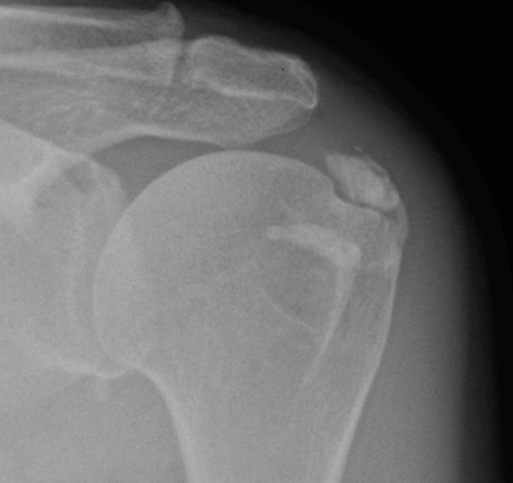

Назначено обследование (рентгенография, МРТ, УЗИ) в ходе которого выявлены очаги кальцификации в области вращательной манжеты левого плечевого сустава.

Фото1. Рентген-снимок левого плечевого сустава пациентки до выполнения процедуры гидроэвакуации.